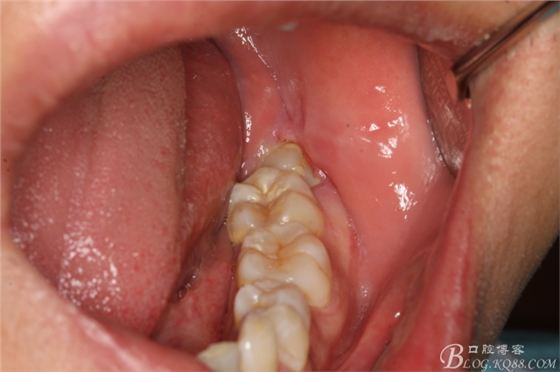

圖1.口內(nèi)觀:38牙冠萌出約1/3,頰側(cè)牙齦輕度紅腫,牙冠低于37合面,屬于中位阻生